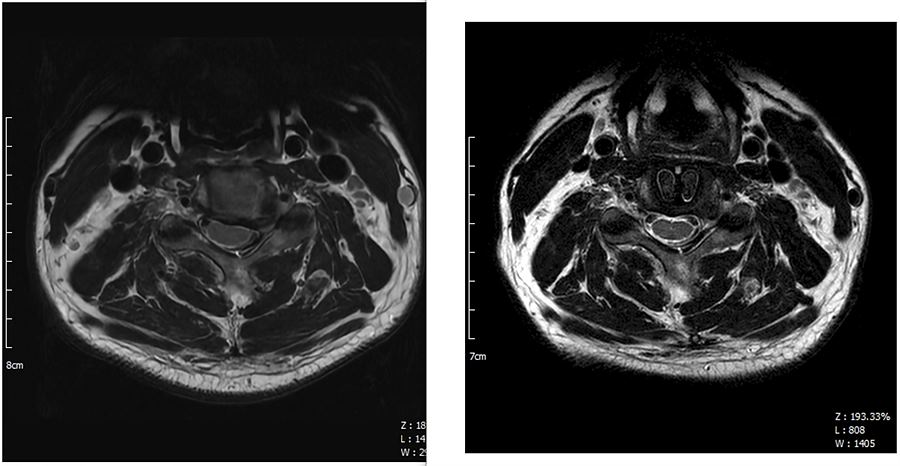

2. MRI 가로 사진 : 오른쪽이 수술후

. C4-C5 사이의 사진.

. 수술 후 디스크 있던 자리에 케이지가 보인다. (Zimmer Biomet Fidji Cervical 14/17/6mm)

. 가운데 척수가 한쪽으로 쏠렸었는데 수술후 약간이지만 가운데로 돌아왔고 공간도 생긴 것이 확인된다.

. 디스크를 모두 걷어내고 왼쪽 신경공을 넓혔지만 워낙 많이 막혀 있었기 때문에 반대편처럼 넓게까지는 안되는것 같다.

. 하지만 아래사진처럼 케이지를 박으면서 높이가 달라져서 그나마 괜찮은 것 같다.

. 오른쪽 신경공은 수술 전후 상관없이 넓다.